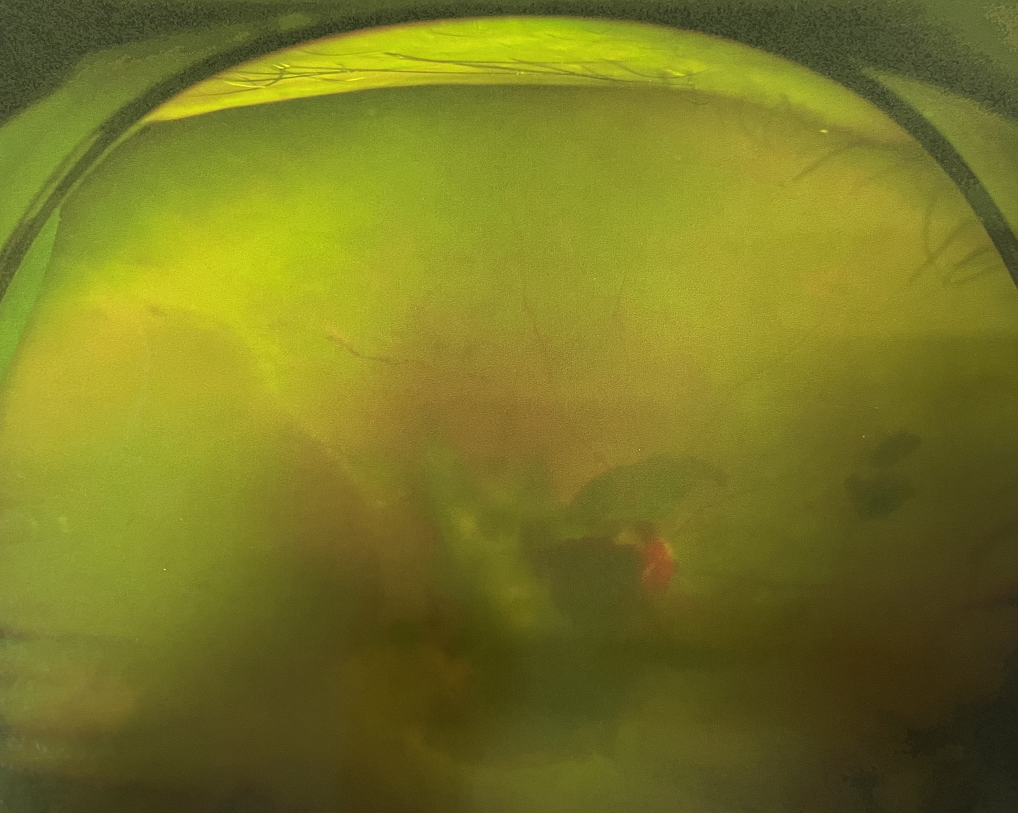

眼底出血多指玻璃體內(nèi),眼睛更深處的視網(wǎng)膜出血。通常情況下,肉眼難以發(fā)現(xiàn)眼底出血,而且發(fā)病初期眼睛也無(wú)明顯癥狀,只有借助專業(yè)的眼底檢查儀器才能觀察到異樣。那么眼底出血嚴(yán)重嗎?

眼底出血嚴(yán)重嗎?對(duì)于已出現(xiàn)黃斑水腫、視網(wǎng)膜新生血管的患者,根據(jù)眼底血管造影、oct等檢查結(jié)果,給予玻璃體腔注射抗VEGF藥物及激光治療,可以減輕黃斑水腫,使視網(wǎng)膜新生血管消退,以免進(jìn)一步發(fā)生玻璃體出血、視網(wǎng)膜脫離等嚴(yán)重并發(fā)癥的出現(xiàn)。對(duì)于玻璃體出血者,傳統(tǒng)認(rèn)為玻璃體出血3-6個(gè)月不吸收再進(jìn)行手術(shù)干預(yù),但近年來(lái)因?yàn)轱@微手術(shù)設(shè)備及玻璃體切割技術(shù)已非常成熟,故對(duì)于1個(gè)月不吸收的玻璃體出血者就可以考慮手術(shù),即手術(shù)時(shí)機(jī)應(yīng)該具體情況具體分析,因人而異。